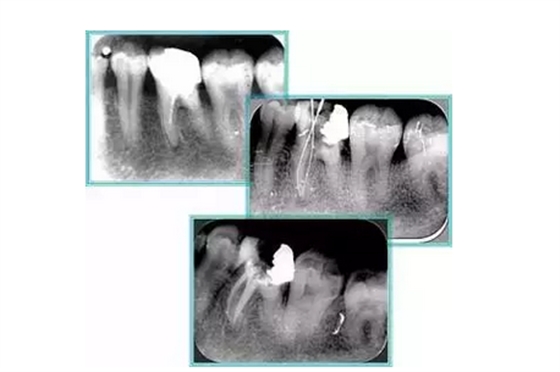

左圖和上圖為干髓治療后牙齒,齲齒疏通后進(jìn)行根管充填。

如圖為塑化加根充處理后牙齒 X 線片。

6. 鈣化

常見有修復(fù)性鈣化和增齡性鈣化。下面為根管鈣化 X 線片。